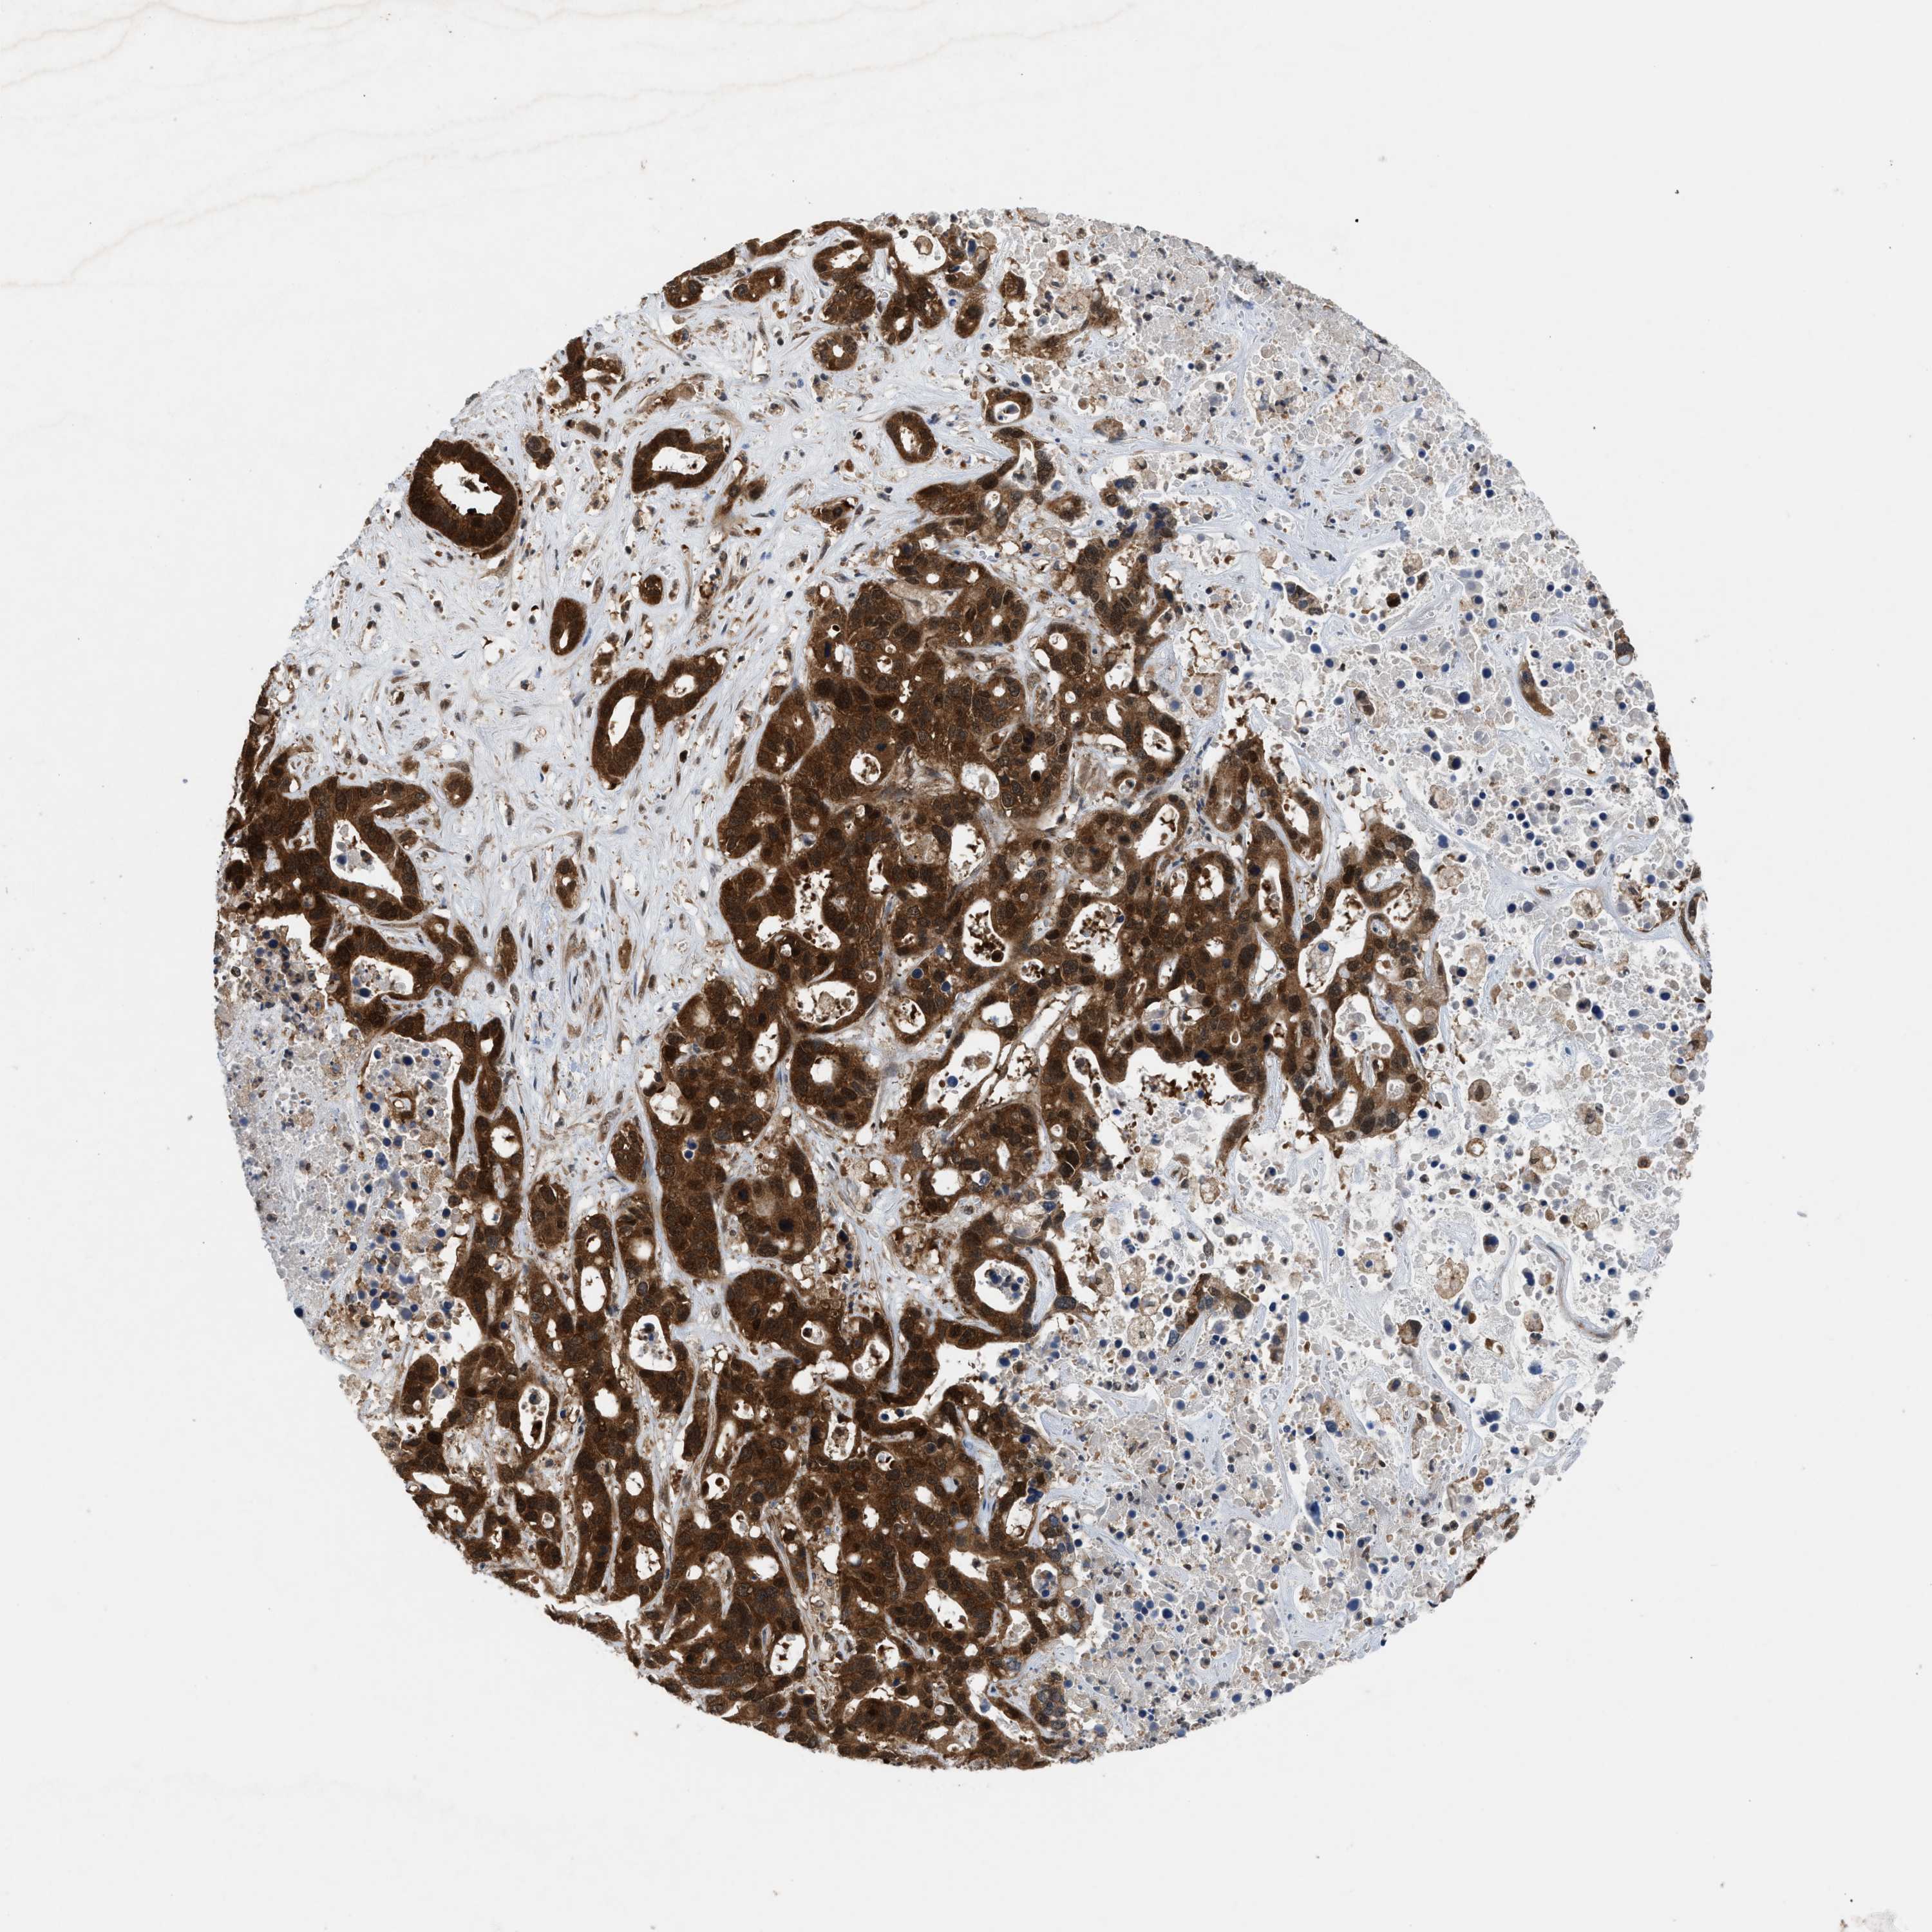

LIVER CANCER - Protein expressioni

A mouse-over function shows sample information and annotation data. Click on an image to view it in a full screen mode. Samples can be filtered based on level of antibody staining by selecting one or several of the following categories: high, medium, low and not detected. The assay and annotation is described here.

Note that samples used for immunohistochemistry by the Human Protein Atlas do not correspond to samples in the TCGA dataset.

Antibody stainingi

Antibody staining in the annotated cell types in the current human tissue is reported as not detected, low, medium, or high, based on conventional immunohistochemistry profiling in selected tissues. This score is based on the combination of the staining intensity and fraction of stained cells.

Each image is clickable and will lead to virtual microscopy that enables deeper exploration of all samples and also displays staining intensity scores, fraction scores and subcellular localization as well as patient and tissue information for each sample.

Antibody HPA008237

Antibody CAB017181

Staining

High

Medium

Low

Not detected

Intensity

Strong

Moderate

Weak

Negative

Quantity

>75%

75%-25%

<25%

None

Location

Nuclear

Cytoplasmic/membranous

Cytoplasmic/membranous,nuclear

Cholangiocarcinoma

Carcinoma, Hepatocellular, NOS